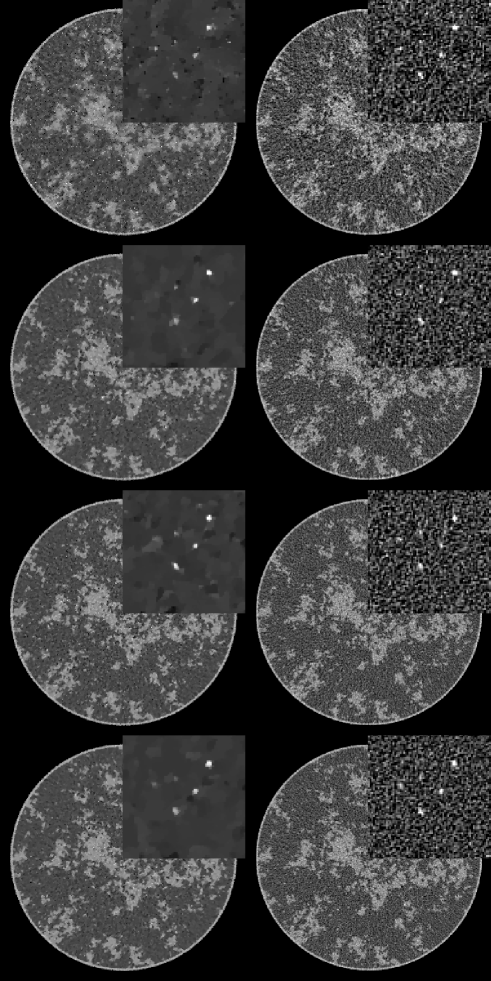

IV-B image reconstruction from noisy data

For the noise studies, we again investigate data sets with the view number varying between 64 and 512. For these reconstructions, is also varied between and . In Fig. 3, we show the TV-minimization images compared with FBP, as a reference. The optimal values of for each TV-minimization image is chosen by visual inspection. The FBP fill images are smoothed by convolving with a Gaussian distribution of width 140 microns (chosen by visual inspection), and the ROI images are unregularized. While it is not too surprising that the FBP image quality appears to increase with projection number, it is somewhat surprising that the same trend is apparent for image reconstruction by TV-minimization. The 512-view data set seems to yield, visually, the optimal result in that the ROI appears to have the least amount of artifacts. While most of the micro-calcifications are visible in each reconstruction, the artifacts and noise texture in the sparse-view images can be distracting and mistaken for additional micro-calcifications. It seems that the increased noise-level per view impacts the reconstruction less than artifacts due to insufficient sampling. That we obtain this result with a CS algorithm is interesting, and warrants further investigation with more rigorous and quantitative evaluation.

To appreciate the impact of , we focus on the 512-view data set and display images in Fig. 4 for three cases. Small corresponds to a tight data constraint, resulting in salt-and-pepper noise in the image due to the high noise-level of the data. Increasing reduces the image noise and eventually removes small structures.